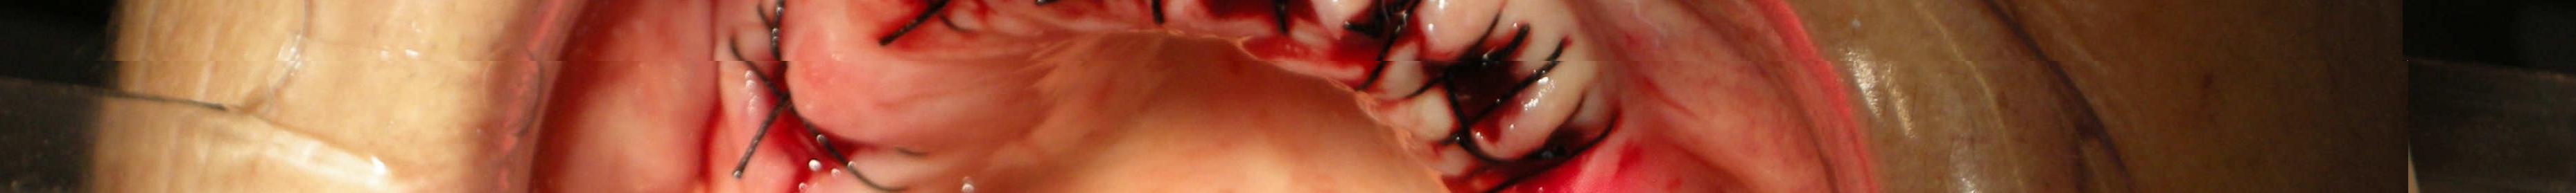

Implantology

Dr. Valter Pirazzoli